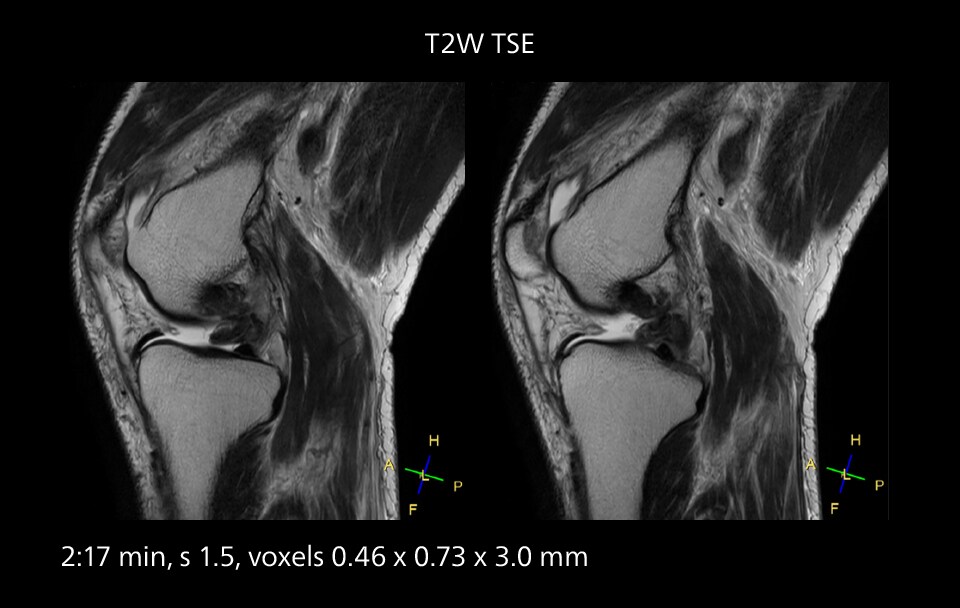

Images showing a posterior cruciate ligament (PCL) tear, a detached medial collateral ligament (MCL) on the tibial side and an intact anterior cruciate ligament (ACL). SmartPath to Elition X helped reduce scan time compared to previous imaging while maintaining resolution.

Sannodai Hospital radiologists had been very satisfied with their Ingenia 3.0T with Compressed SENSE, however after acquiring SmartPath to Elition X they have demonstrated improved image quality and even higher speeds in imaging studies throughout the body, according to Dr. Makuuchi. “Generally, we were impressed by seeing that images are very sharp and have higher SNR than we used to get with our Ingenia 3.0T system,” he notes. “We were delighted to see that high image quality can be obtained in a short time thanks to the Elition with its powerful An example of increased imaging speed is in knee studies. “There is a definite scan time reduction for T2* mFFE and proton density TSE – both of these sequences benefit from much shorter repetition times,” he reports.